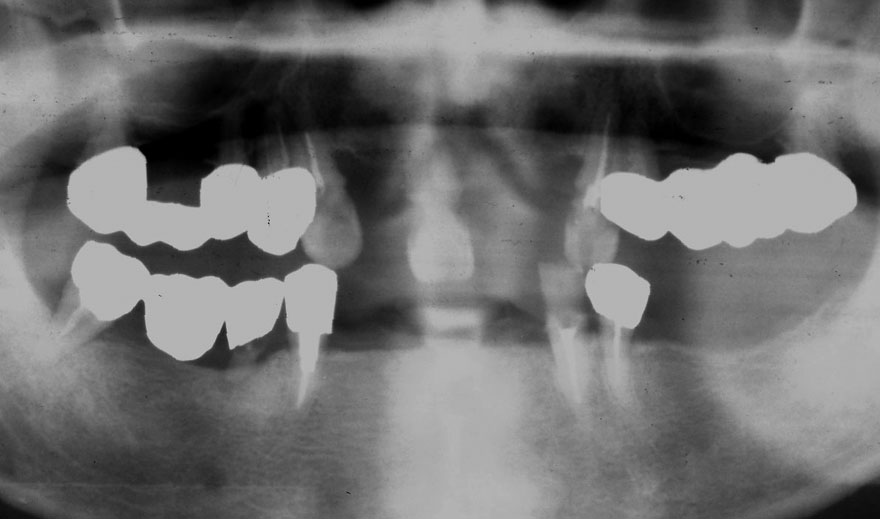

初診時 52歳 女性 平均歯槽骨喪失量:4.75mm

河田歯科医院

24年後 74歳

平均歯槽骨喪失量:6.13mm

21年間喪失量:-1.38mm

年間喪失速度:-0.057mm

(ケア頻度:1.25ヵ月ごと)